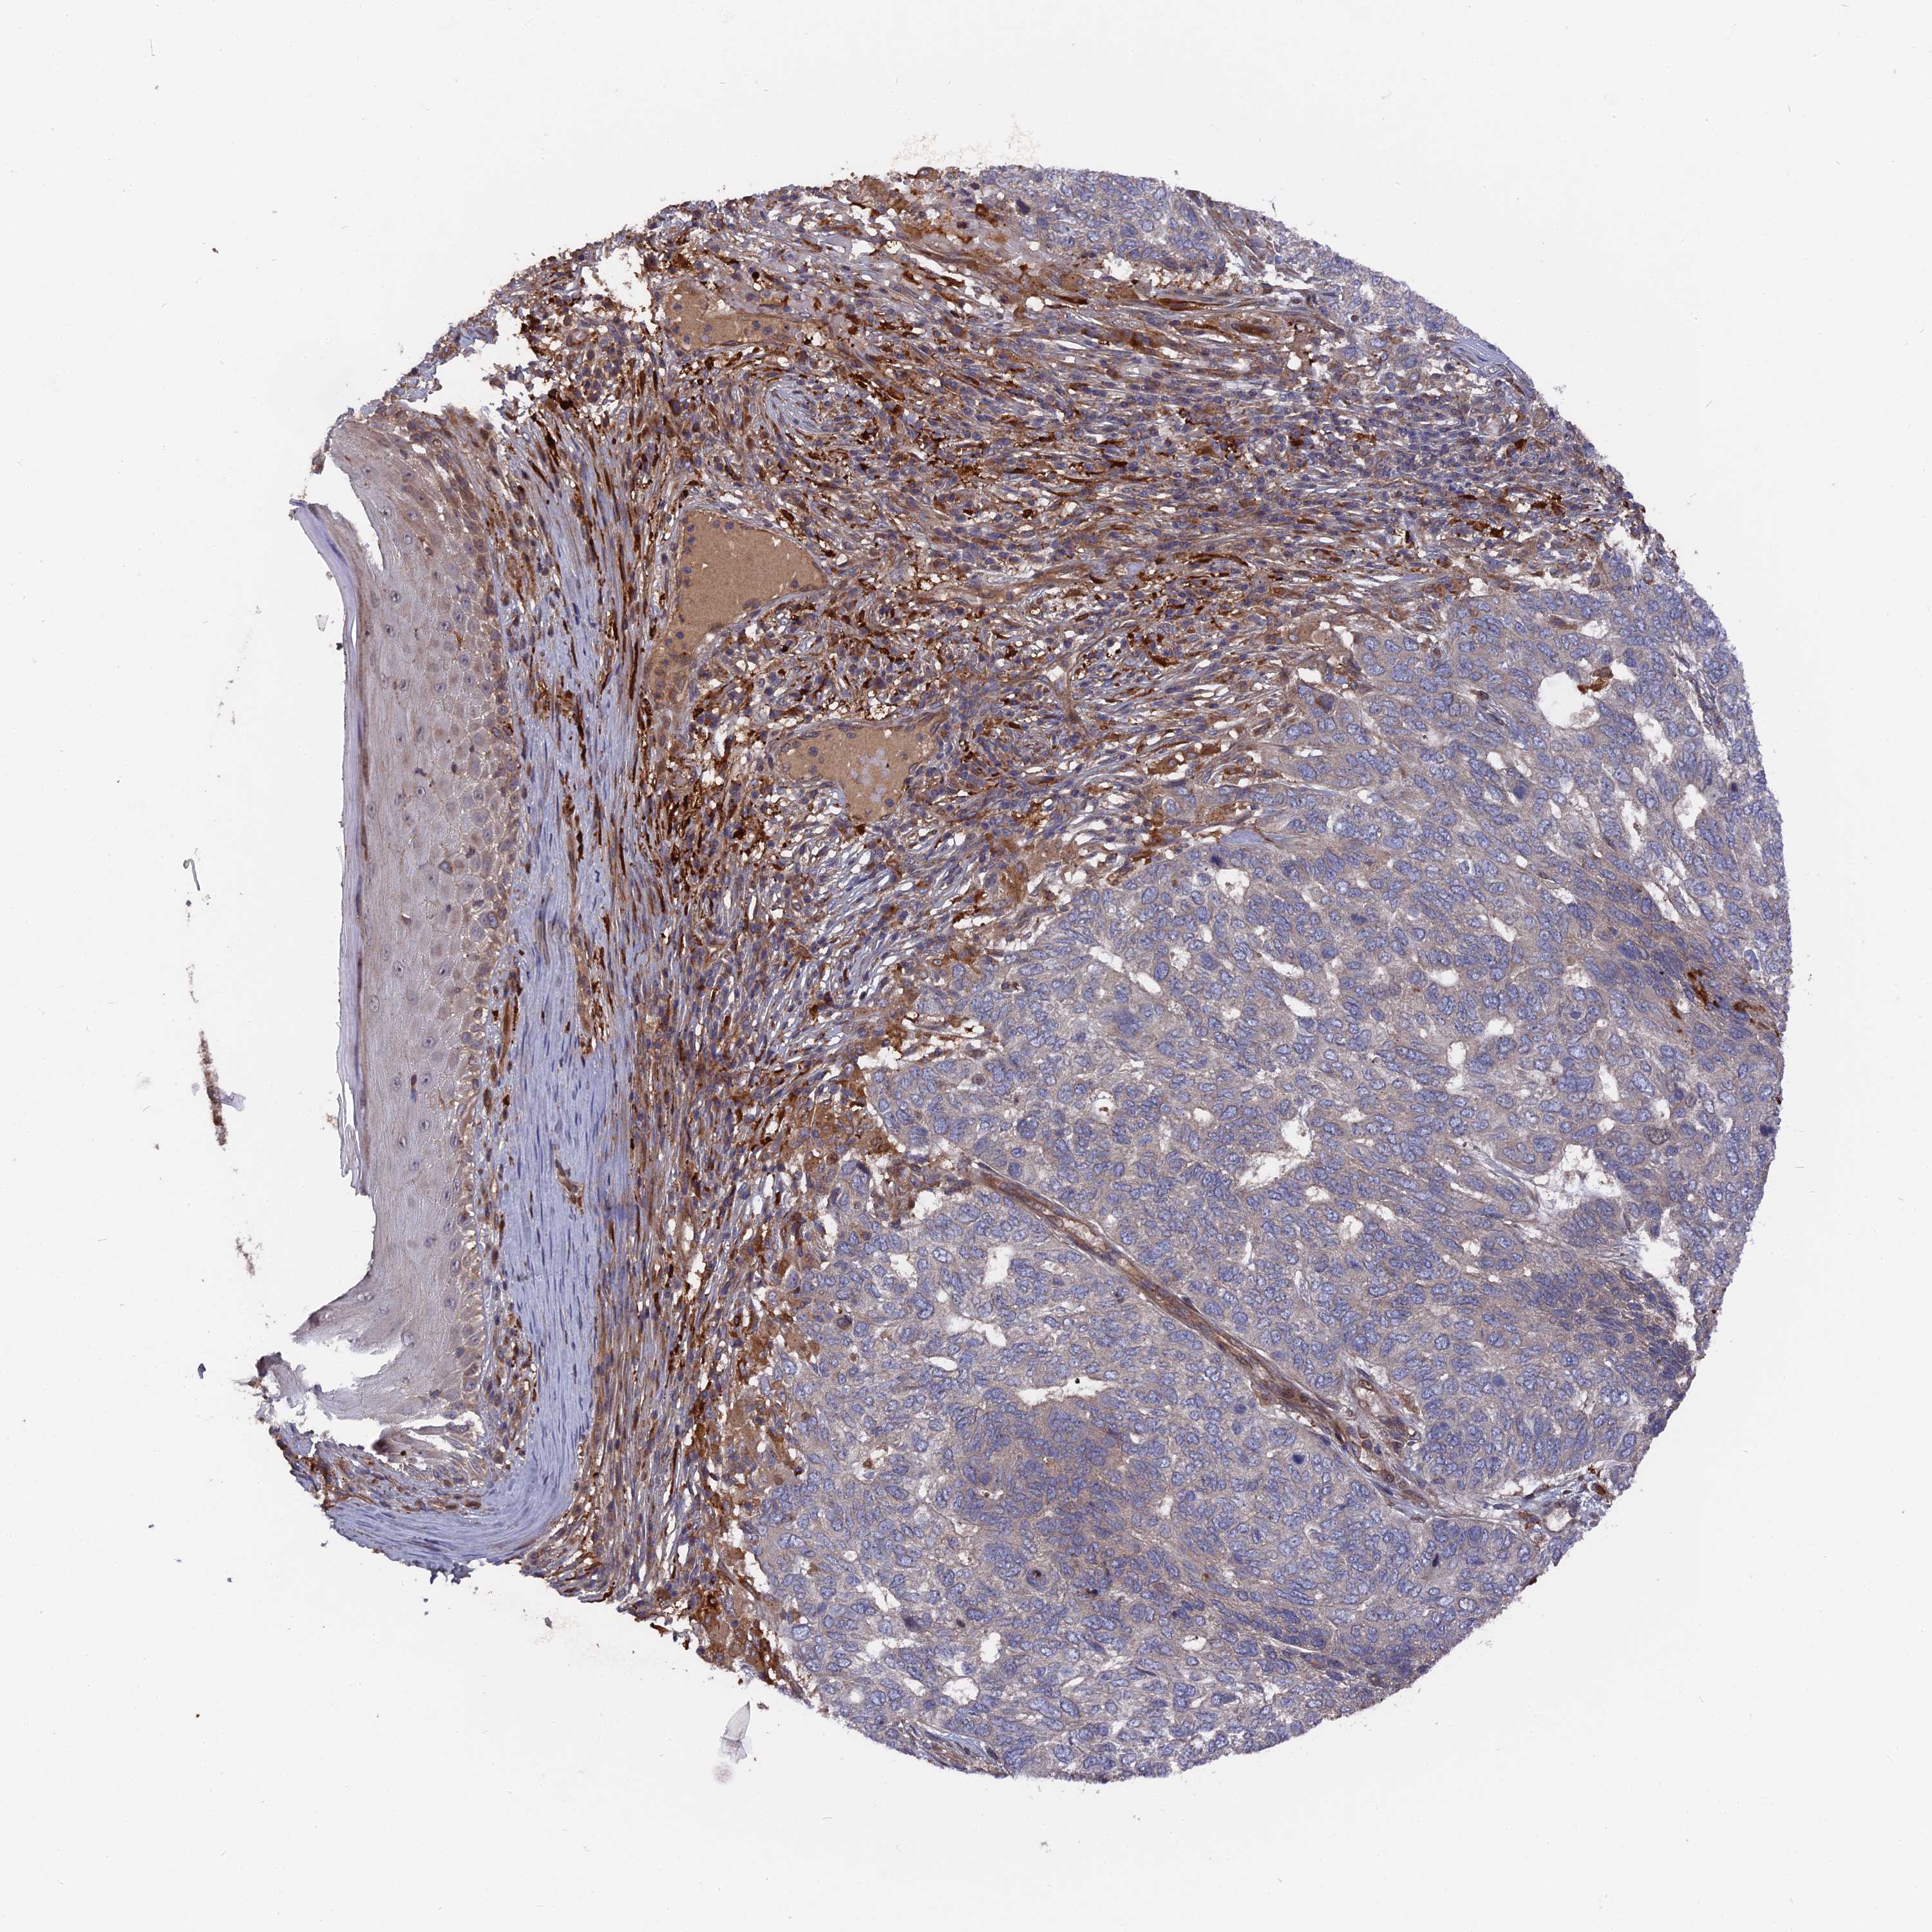

SKIN CANCER - Protein expressioni

A mouse-over function shows sample information and annotation data. Click on an image to view it in a full screen mode. Samples can be filtered based on level of antibody staining by selecting one or several of the following categories: high, medium, low and not detected. The assay and annotation is described here.

Antibody stainingi

Antibody staining in the annotated cell types in the current human tissue is reported as not detected, low, medium, or high, based on conventional immunohistochemistry profiling in selected tissues. This score is based on the combination of the staining intensity and fraction of stained cells.

Each image is clickable and will lead to virtual microscopy that enables deeper exploration of all samples and also displays staining intensity scores, fraction scores and subcellular localization as well as patient and tissue information for each sample.

Antibody HPA041745

Staining

High

Medium

Low

Not detected

Intensity

Strong

Moderate

Weak

Negative

Quantity

>75%

75%-25%

<25%

None

Location

Nuclear

Cytoplasmic/membranous

Cytoplasmic/membranous,nuclear

Squamous cell carcinoma, NOS

Squamous cell carcinoma, metastatic, NOS